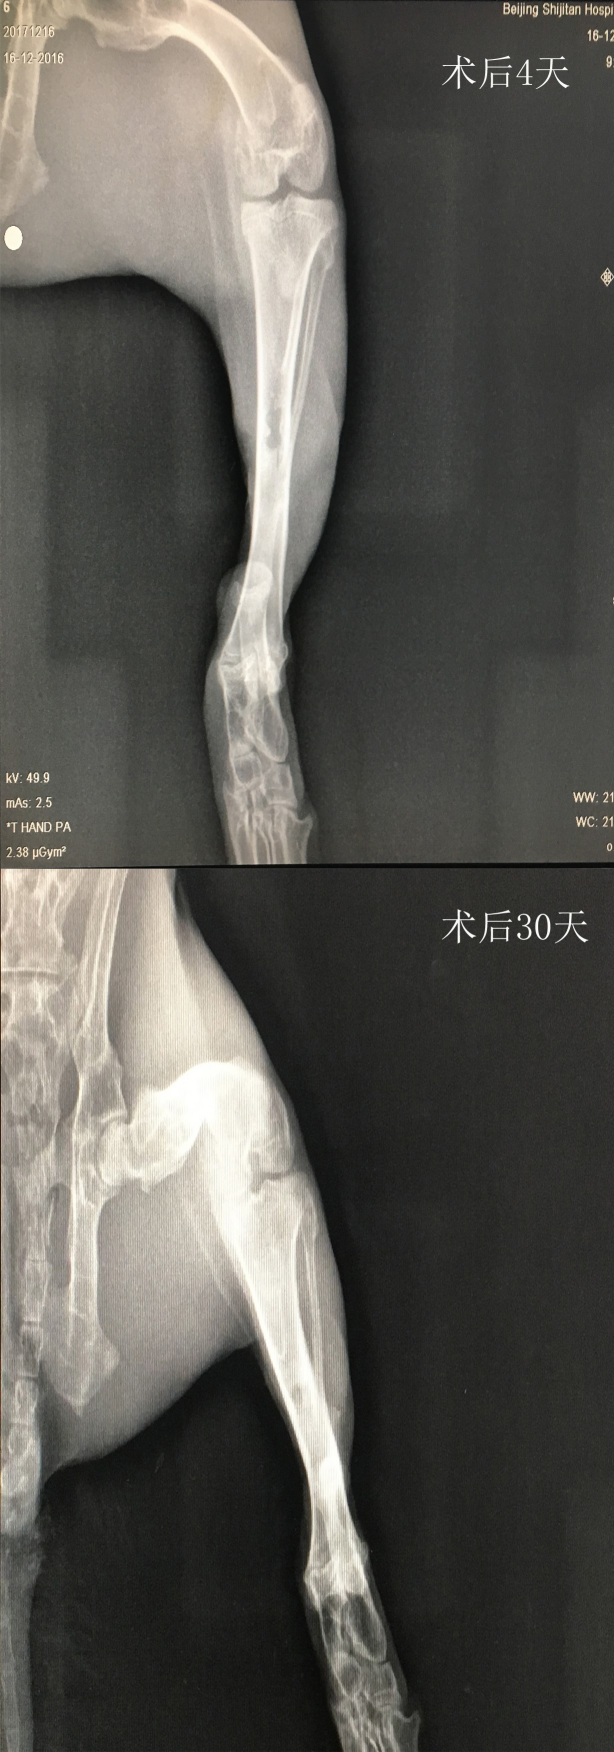

X光

2.肿瘤动物模型:在肿瘤动物模型实验中,X光技术可以与药物联用,用于肿瘤药物和治疗方法的开发、研究与评估,以及放疗的机制和方法研究。